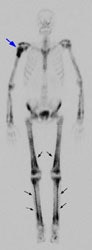

Example 2: This is an interesting case of a patient with non-small-cell lung cancer who complained of right shoulder pain. The bone scan demonstrates a bone lesion in the proximal right humerus (blue arrow) consistent with a metastasis. The scan also revealed linear uptake of tracer along the distal femurs and tibias bilaterally (black arrows). Uptake in the forearms was more irregular. A coned down plain film of the distal left femur demonstrated a solid periosteal reaction (white arrows). The findings are consistent with hypertrophic osteoarthropathy- a paraneoplastic condition seen in association with bronchogenic carcinoma.

NOTE: Click directly on the image to enlarge.